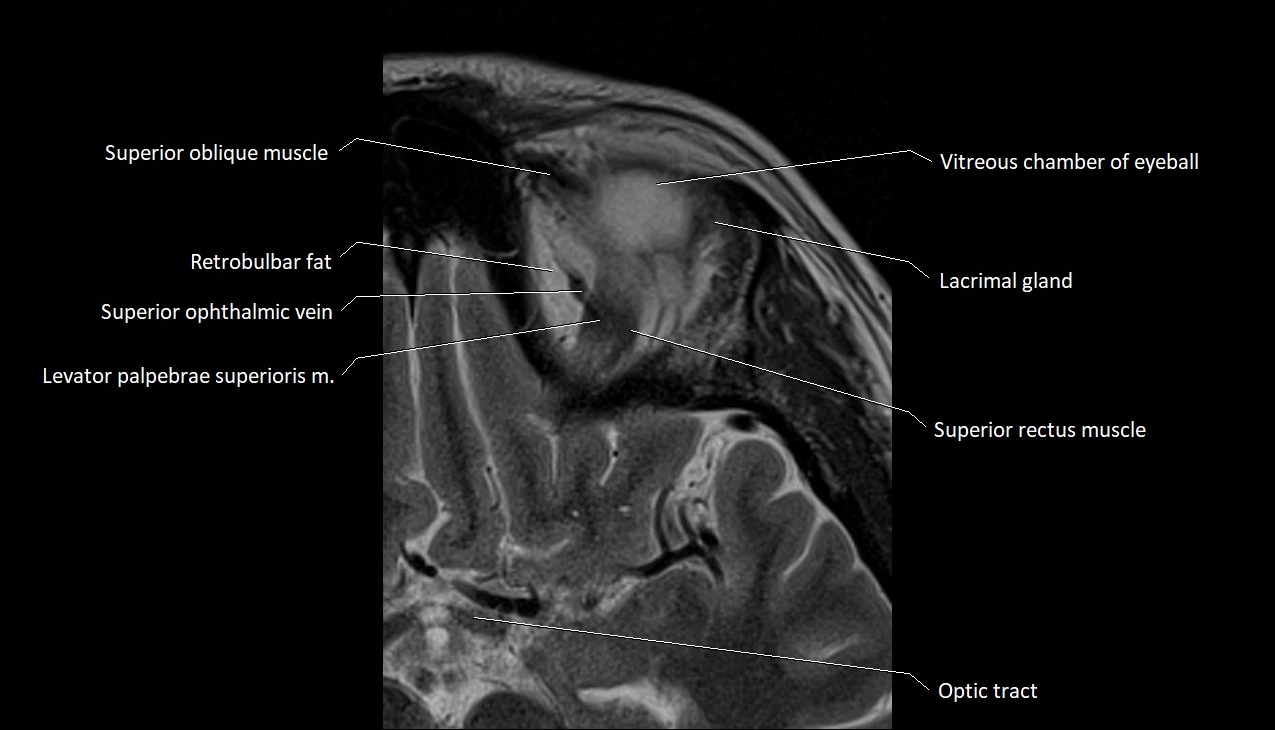

MRI images